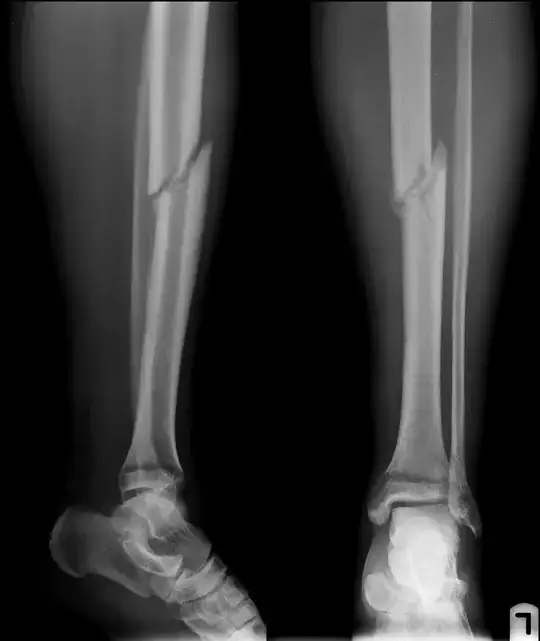

If you look at your radiographs, you can see the callus forming, so long answer short, yes, your fracture(s) are healing. It will take a long time to look healed - about a year - on x-ray.

"Breaking" the fibula (or fibular ostotomy) in cases of tibial non-union is not unheard of, but I have absolutely no idea of how often it's done, or if the additional weight-bearing associated with it speeds tibial healing. But please note that you already have an angulated distal fibular fracture (look at the bone - the fibula - behind the tibia just above its concave surface in the leg on the left.) It looks to be at about 20°.

Also note that the tibial stress fractures - the fracture lines perpendicular to the plane of the tibial fracture itself - are more prominent in the second set of x-rays (this may just be picture quality), as well as more prominent displacement of your fracture, which is easier to see if you follow the medullary lines - the "hollow" inner part of the bone where the bone marrow is - you'll see they line up nicely in the first set of x-rays, less so in the second.